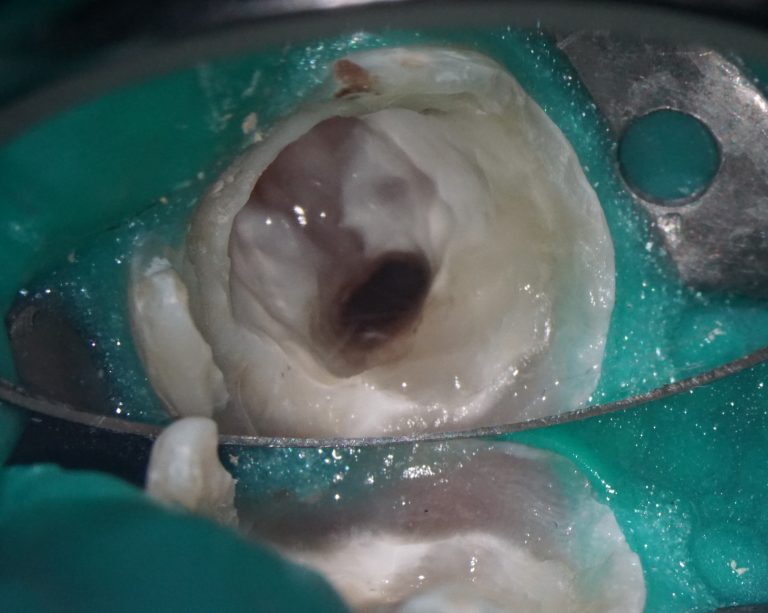

The second mesio-buccal (MB2) canal is notorious for being difficult to identify and is often left untreated, this can directly influence the outcome of the final treatment

Diagnocat AI helps us to see not only the consequences, but also the causes of the pathology. For example, in this clinical case – the missed MB2 during previous endodontic treatment of tooth 26 (Universal 14)